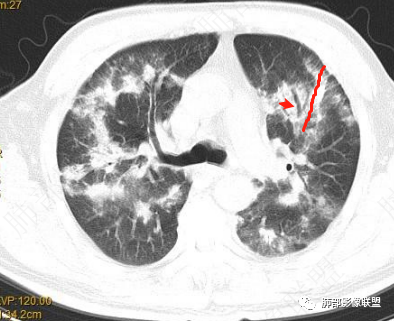

肺部弥漫病灶,斑片、条带为主。似有一些结节灶。

这些病灶的特点:

1、部分沿支气管血管束分布,内部支气管通畅,稍扩张。

2、部分外带(距离胸膜下有间隙),与胸膜平行

部分环形融合

首先病灶是距离胸膜有间隙为主,其次是侧向融合,导致长轴与胸膜平行

距离胸膜的位置——提示小叶核心病灶

侧向融合

提示病灶位于小叶核心,逐步增大,到了一定大小之后相互连接,也就是侧向融合

还没有融合的

已经融合的

相对而言:已经融合的,边缘平直、光滑一些,周围纤维化明显一些,没融合的边缘模糊一些,周围GGO多一些;提示融合的病灶更早,已经开始有纤维化改变特点;而没融合的属于后发一些的病灶,纤维成分还不够

提示融合:除了有病灶增大的原因,与纤维化也很大关系

至于这种反晕征状:我认为是外周一层的小叶核心病灶与偏内侧的小叶核心病灶的融合,不是大片状病灶周围的修复所指。

2022.2.17CT显示两肺中内带多发结节影、斑片影、条索影,部分病灶侧向融合与胸膜平行。部分病灶沿着支气管血管束分布、其内支气管稍扩张。部分病灶呈反晕征。大部分病灶边界显示清晰,部分病灶周围可见边界不清的GGO。2022.4.12CT显示两肺中内带多发结节影、条索状、条带状高密度影,边界收缩平直凹陷,大部分病灶沿着支气管血管束分布,亦有位于胸膜下侧向融合与胸膜平行的病灶。总体与第一次CT对比两肺病灶明显吸收。